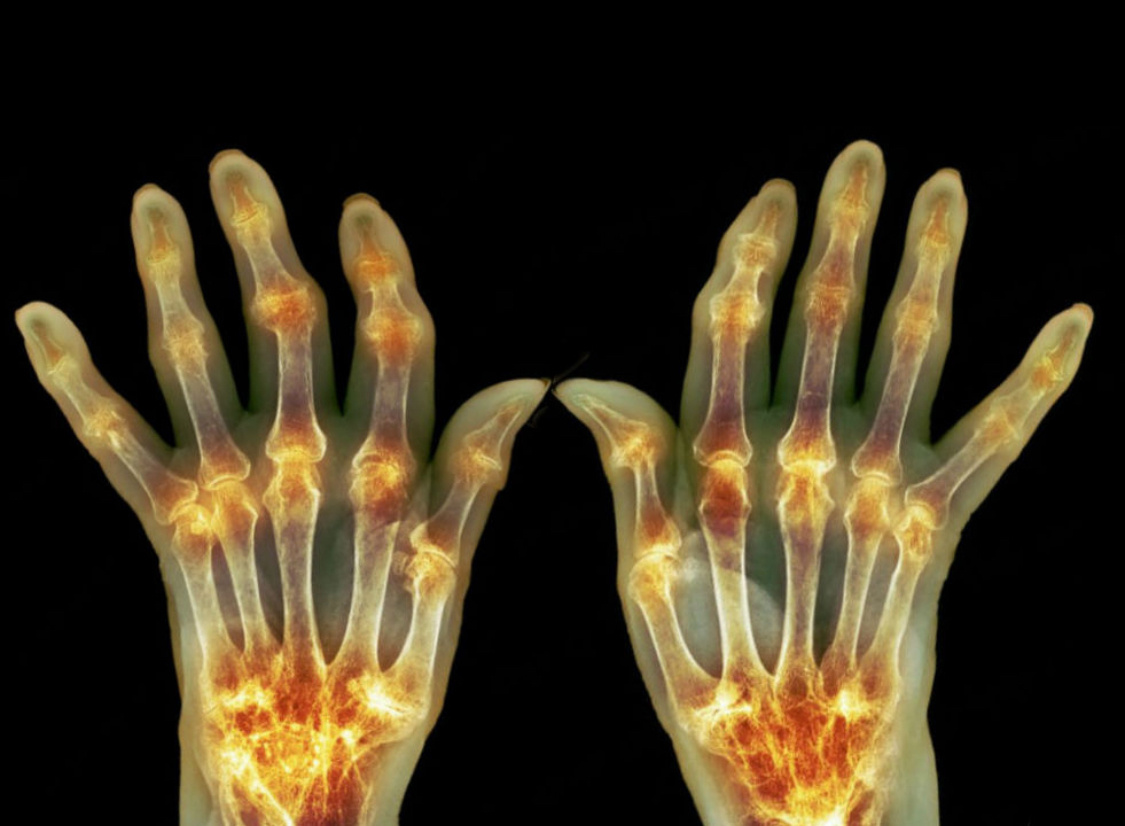

Когда-то давным-давно, во времена моего обучения в ординатуре на базе ревмоортопедического отделения, услышал от пожилых врачей странную штуку. Якобы у пациентов с ревматоидным полиартритом (это когда много суставов одновременно воспалены постоянно) воспаление напрямую связано с настроением. То есть, если у больного стресс, отрицательные эмоции - тут же обостряется ревматоид. Всё хорошо, человек на позитиве - и суставы ведут себя прилично. Сначала я эту информацию пропустил мимо ушей, но потом неоднократно слышал то же самое уже от самих пациентов. А потом еще и статейку где-то прочёл иностранную примерно о том же самом. Собственно говоря, логически всё объяснимо. Вся наша жизнь - биохимия. Страх - адреналин - спазм сосудов - ишемия мозга/миокарда - инсульт/инфаркт. Примерно то же самое с любовью - там свои гормоны, и всеми другими чувствами. То есть, любая наша эмоция сопровождается повышенной выработкой химических веществ, а уж этих веществ у нас миллион! Сегодня читаю следующее: За

Когда-то давным-давно, во времена моего обучения в ординатуре на базе ревмоортопедического отделения, услышал от пожилых врачей странную штуку. Якобы у пациентов с ревматоидным полиартритом (это когда много суставов одновременно воспалены постоянно) воспаление напрямую связано с настроением. То есть, если у больного стресс, отрицательные эмоции - тут же обостряется ревматоид. Всё хорошо, человек на позитиве - и суставы ведут себя прилично. Сначала я эту информацию пропустил мимо ушей, но потом неоднократно слышал то же самое уже от самих пациентов. А потом еще и статейку где-то прочёл иностранную примерно о том же самом.